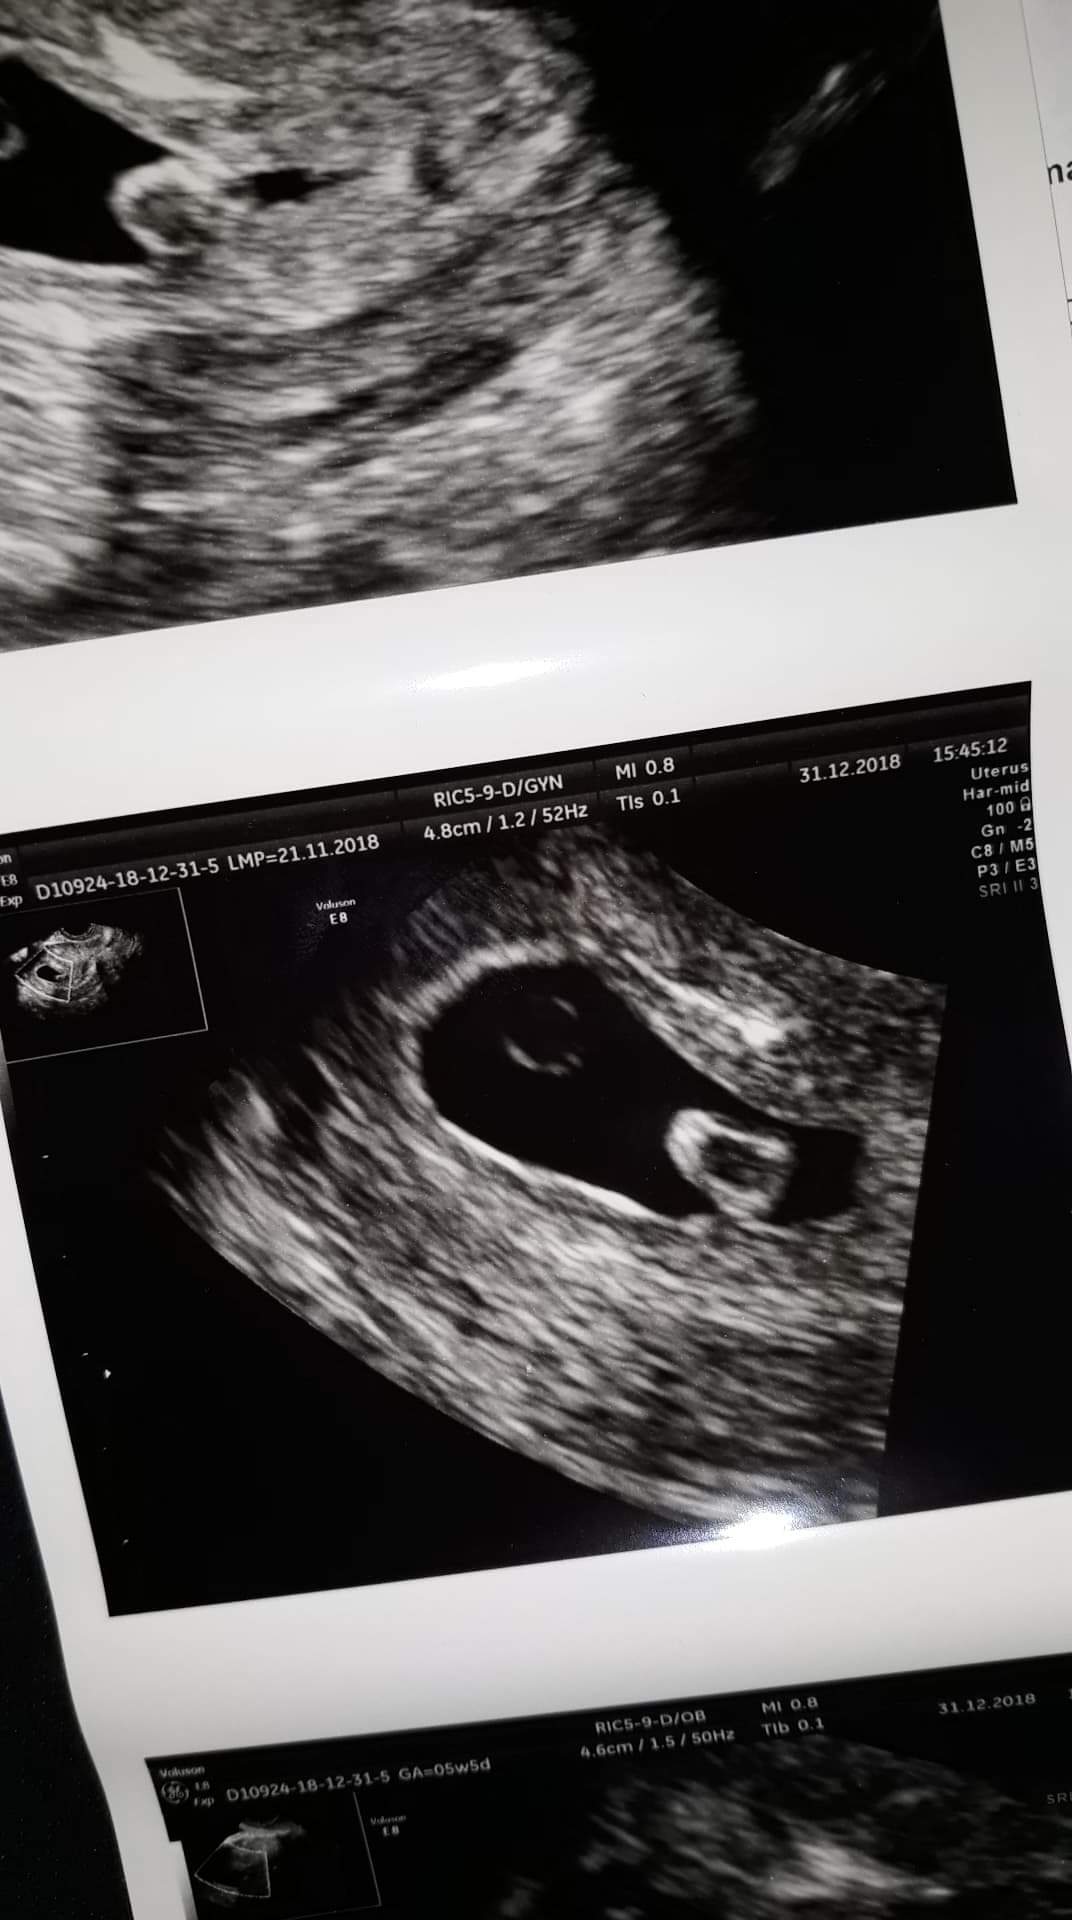

Witam, 2 tygodnie temu podczas usg, lekarz zauważył pecherzyk ciazowy, ale po przeciwnej stronie jakis twór o srednicy 7mm. Kazał pokazac sie za tydzien, na usg widac bylo bicie serca dziecka, ale ten twór nie zniknął, ale też nie urósł, dalej ma 7mm. Jest unaczyniony. Czy ktos spotkał sie z czymś podobnym? Lekarz zaśniad raczej wyklucza, bo hcg nie rosnie na tyle szybko. Prosze o jak najszybszą odpowiedź. Pozdrawiam i załączam 2 zdjecia z usg :)

received_559220414489326.jpeg